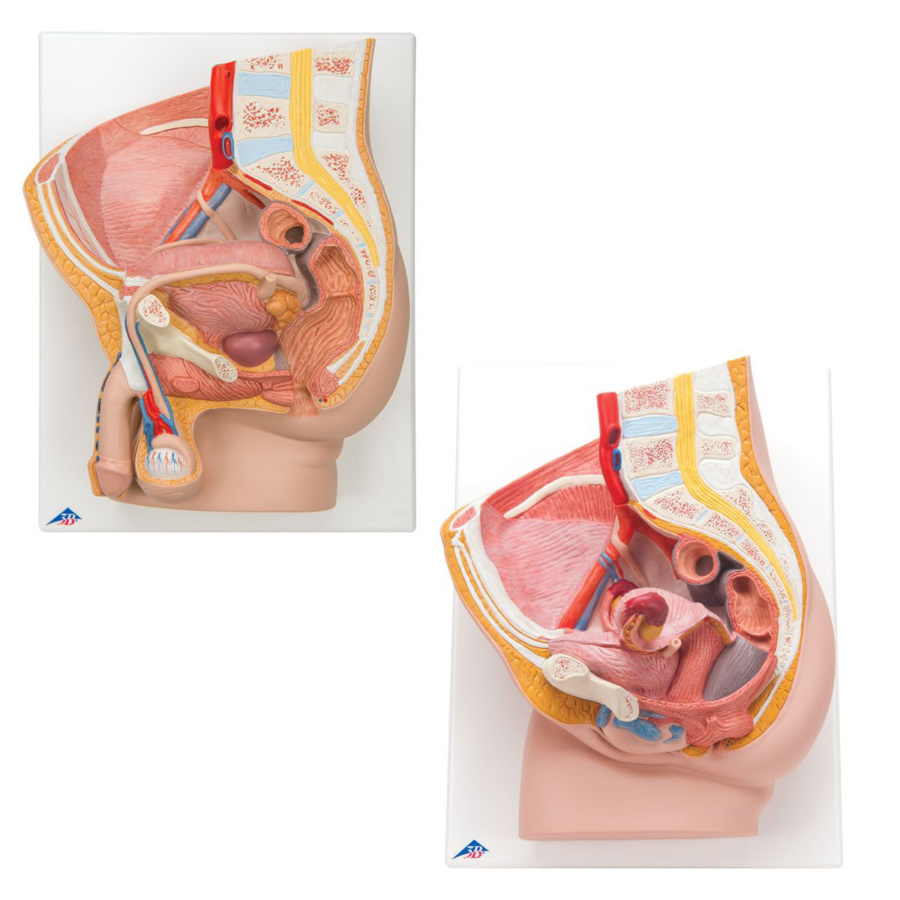

沸騰ブラドン 女性骨盤モデル(可動型) 日本スリービー 25-3004-00 人体模型 人体模型の詳細情報

女性骨盤モデル(可動型) 人体模型 25-3004-00 日本スリービー。8000837-900x900.jpg。Amazon.co.jp: 実物大の女性骨盤模型 - 女性骨盤モデル,大腿骨。BEURRE 焼酎 3本セット。解剖学的教育に最適な骨盤模型、NFC機能付き。女性骨盤モデル,大腿骨付 | 日本スリービー・サイエンティフィック。女性日本スリービー・サイエンティフィック株式会社定価1.8万ほどで購入- モデル: 骨盤模型- 特徴: NFC機能付き- 用途: 解剖学的教育用- 材質: プラスチック- サイズ: 約30cm x 20cmご覧いただきありがとうございます。タケヤ式自在置物 骸骨 鉄錆地調 KT Project KT-005。